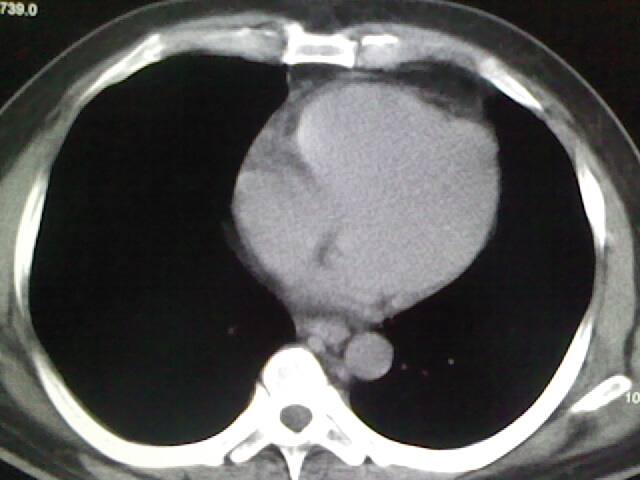

标题: CT17932:临床怀疑肺栓塞

男,34岁,自觉右侧胸痹,胸闷3天余

左上肺局限片状透光度增强区,肺纹理稀少,可考虑局限性肺气肿。

左上肺局限性肺透光度减低,肺纹理稀少;这虽然符合早期肺栓塞的改变,但与局限性肺气肿难以鉴别。

书上讲早期肺栓塞就是表现肺透光度减低,肺纹稀少。